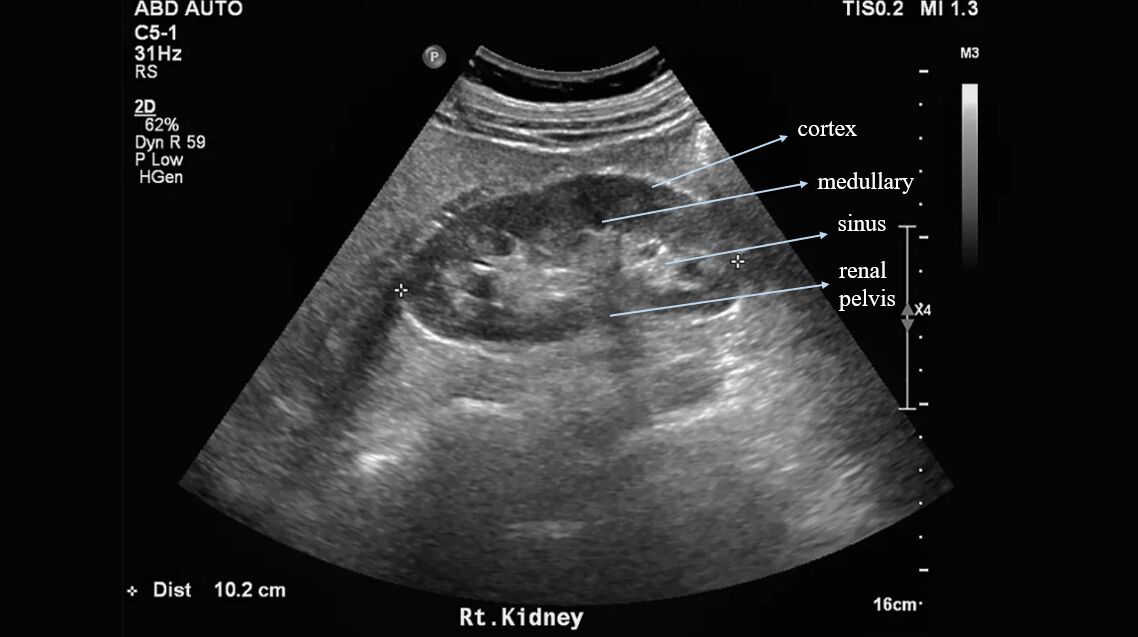

68.附圖中箭號所指高回音的部位最可能為何?

(B)腎竇部(renal sinus)

腎臟的結構如下圖

回音大到小:腎竇-->肝-->脾-->腎皮質-->腎髓質

因為腎竇內含脂肪,所以回音最強